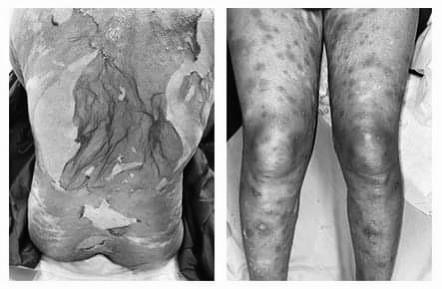

Bệnh bắt đầu 9 ngày trước khi nhập viện. Khởi phát, bệnh nhân xuất hiện các dát đỏ ngứa nhiều ở lòng bàn tay hai bên, sau 3 ngày, thương tổn tiến triển thành mụn nước, bọng nước nông, dễ vỡ, khi vỡ để lại các vết trợt.

Theo thời gian, các thương tổn có tính chất tương tự xuất hiện thêm ở lòng bàn chân hai bên, thân mình, tay, chân, hoại tử da lan rộng. Các niêm mạc không có thương tổn. Bệnh nhân đau rát nhiều. Bác sĩ khám thấy bệnh nhân tỉnh táo, tiếp xúc được, sốt cao, thay đổi mạch, huyết áp. Xét nghiệm có tăng nhẹ men gan, rối loạn chức năng gan.

Bệnh nhân được chẩn đoán hoại tử thượng bì nhiễm độc (hội chứng Lyell) và điều trị tích cực tại khoa, dùng các thuốc đặc hiệu (cyclosporin A) kèm chăm sóc hỗ trợ. Sau 10 ngày điều trị, thương tổn da khô, bắt đầu tái tạo thượng bì, không có bọng nước mới.